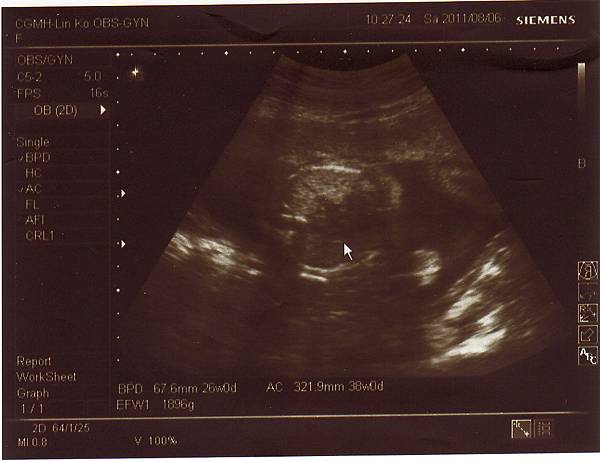

2011.08.06 26週 例行性產檢

終於今天產檢,問了醫生寶寶大小,

醫生說大約九百多克,和同期的寶寶比起來重量也不輕,

而兔妹妹的發展也符合懷孕週數,